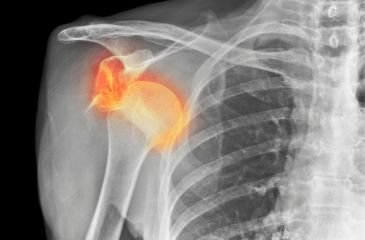

Total Shoulder Replacement

Total shoulder replacement is performed when shoulder arthritis causes persistent pain and limited movement. The damaged joint surfaces are replaced to improve mobility and reduce discomfort.

Rotator Cuff Repair

Rotator cuff injuries cause shoulder pain, weakness, and difficulty lifting the arm. Repair surgery reattaches the torn tendon to restore shoulder strength and function.

Shoulder Dislocation

Shoulder dislocation occurs when the upper arm bone slips out of its socket. Repeated dislocations may require surgical stabilization to prevent further injury and restore confidence in movement.

Frozen Shoulder

Frozen shoulder causes pain and gradual stiffness of the joint. Treatment may include medication, physiotherapy, injections, or minimally invasive procedures depending on severity.